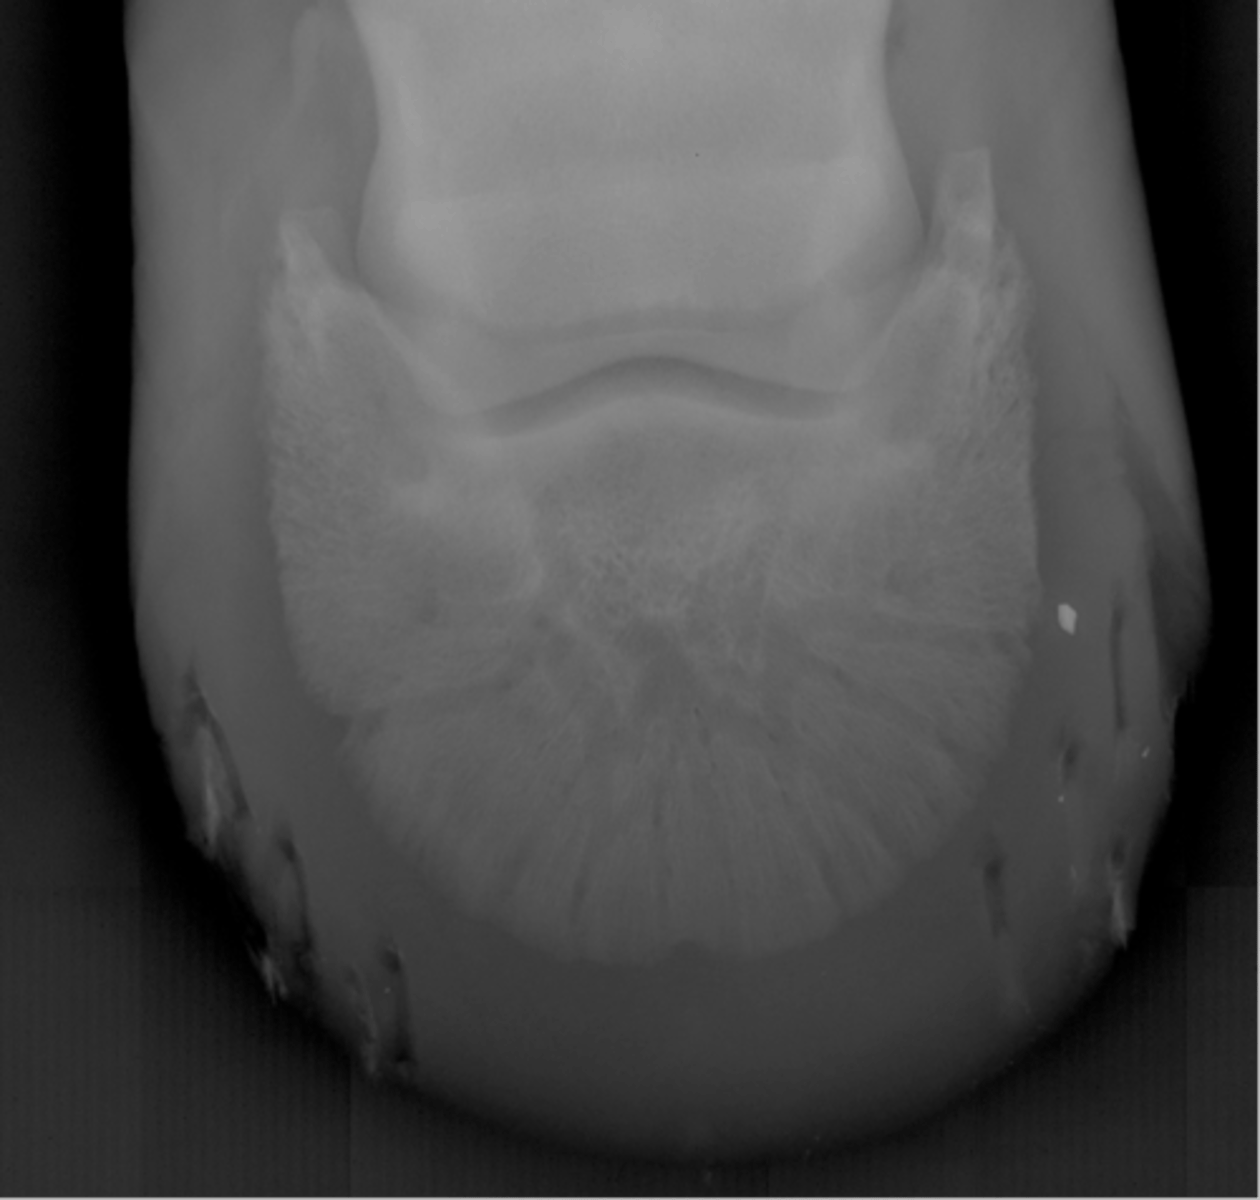

Coffin bone

Navicular bone

Crena

Vascular channelsv

Solar canal

Navicular bone

Flexor cortex

Navicular bone

Proximal border of navicular bone

Distal border of navicular bone

Synovial invaginations

Flexor skyline

What view is this?

1. Flexor surface

2. Corticomedullary distinction

3. Number of synovial invaginations

What is the flexor skyline used to evaluate?

Navicular bone

Articular surface of navicular bone

Flexor surface of navicular bone

Sagittal ridge

Synovial invaginations

Palmar process of P3

Palmar aspect of P2